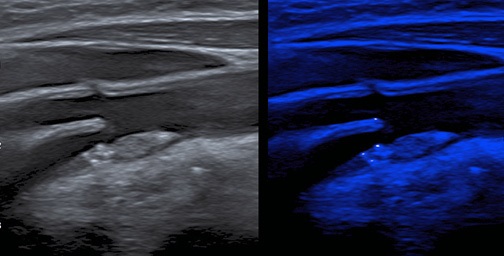

УЗИ экстракраниального отдела брахиоцефальных артерий проводили на ультразвуковом сканере Canon Aplio a550 (Япония), с линейным датчиком с частотой 14,0 МГц. АСБ считали локальное образование, выступающее в просвет артерии как минимум на 0,5 мм от величины окружающей толщины комплекса интима-медиа (ТИМ), или на величину, равную 50% от величины окружающей ТИМ, или образование с увеличением ТИМ >1,5 мм. Степень стенозирования СА определяли по критериям ECST (European Carotid Surgery Trial) (исходный диаметр артерии в месте стеноза/диаметр просвета артерии в месте стеноза × 100%). Визуализацию выявленных АСБ проводили в В-режиме и режиме MicroPure, где оценивалось наличие микрокальцинатов (МК), отображаемых в виде точечных флуоресцентных сигналов на синем фоне (рис. 1). Оценивали факт наличия МК в АСБ, количество МК (единичные или множественные), локализацию МК в АСБ (в покрышке, в теле, в основании, сочетанная локализация). Множественные МК определяли при наличии ≥3 флуоресцентных сигналов в АСБ [7]. Клиническая характеристика больных, включенных в исследование, представлена в таблице 1.

Рис. 1. Ультразвуковое изображение АСБ в области бифуркации общей СА и устье внутренней СА в двойном режиме: слева изображение в В-режиме, справа — в режиме MicroPure.

Примечание: цветное изображение доступно в электронной версии журнала.